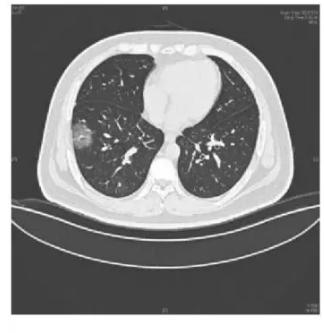

下面这个是新冠肺炎的多发结节影。普通的肺炎也会表现为结节,但是表现为双肺多发结节者不多见。

图13